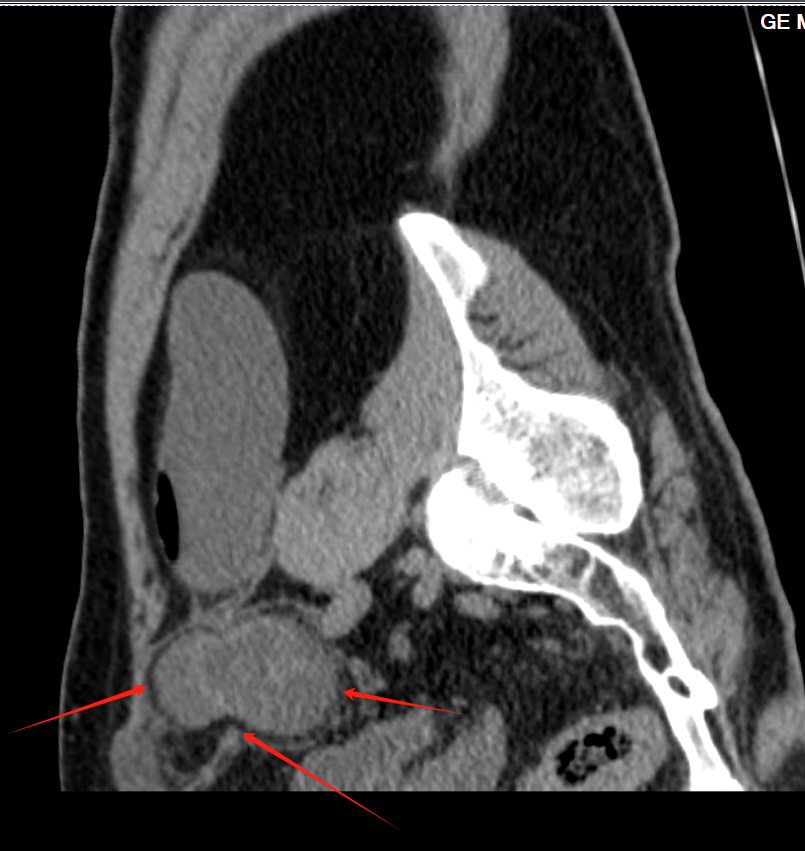

经过外科团队的进一步检查,明确了“左侧嵌顿性腹股沟直疝”的诊断(患者情况紧急,如不及时处理,可能引发肠缺血、坏死等严重后果。)